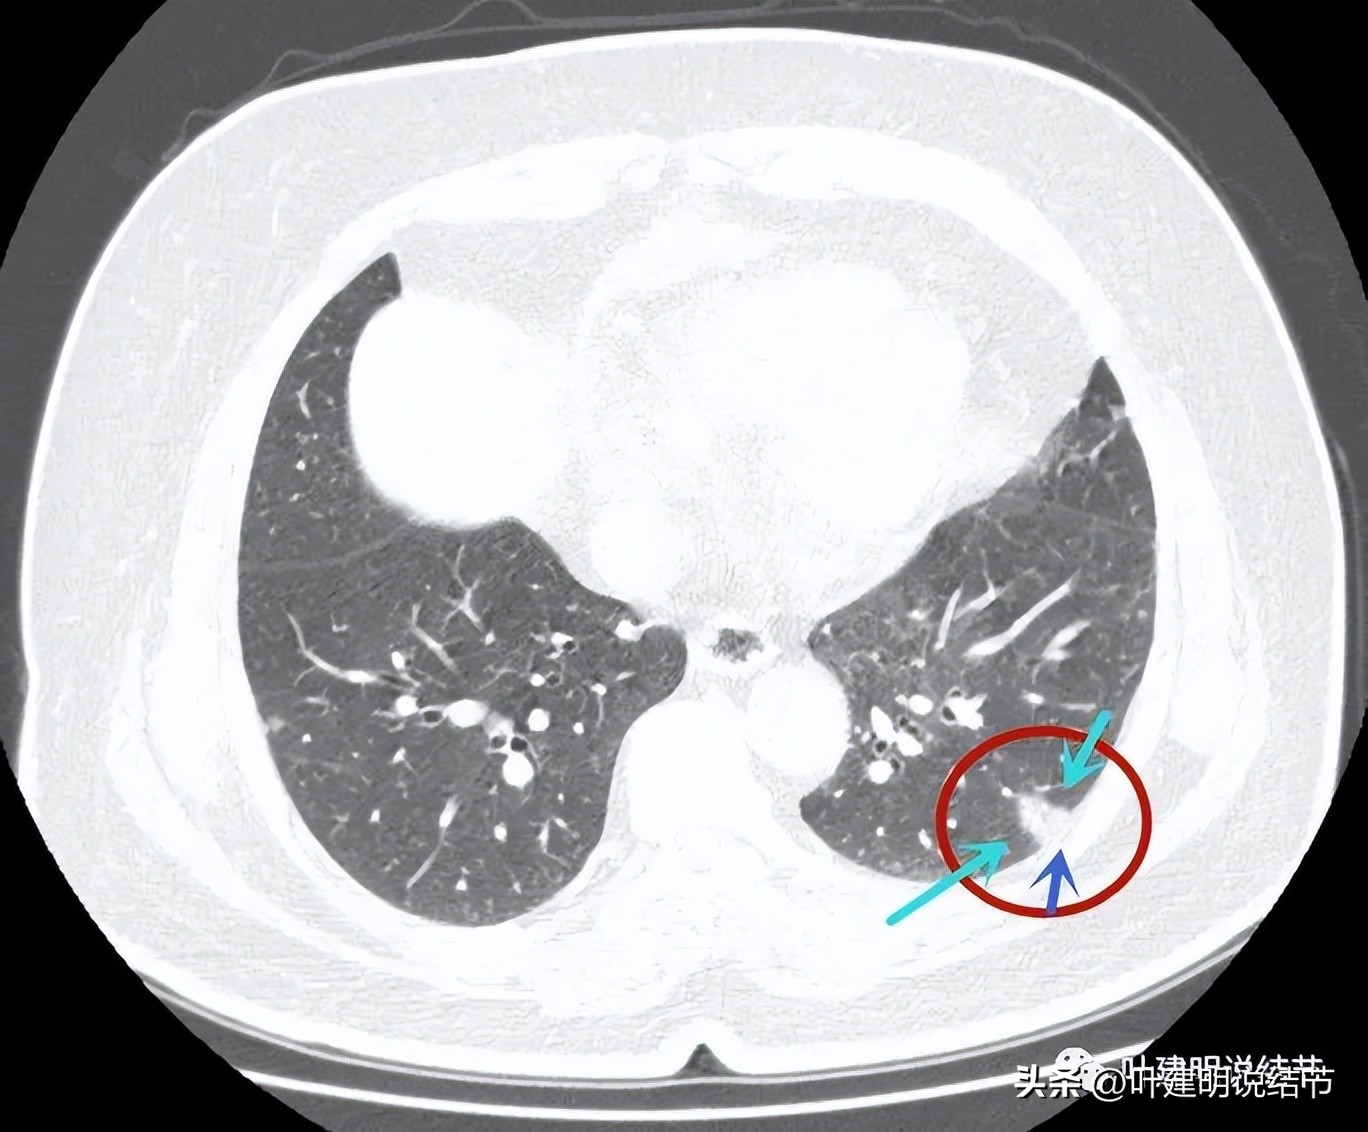

病灶4:左下叶实性结节,即主病灶,实性不是很致密的病灶,胸膜下,边界较清,邻近胸膜没有牵拉。有恶性可能性(良性的用什么疾病能解释?好像错构瘤、硬化性血管瘤、结核、肉芽肿性炎、淋巴结、急性炎症、隐球菌等常见的都靠不太上)。

病灶4:见有血管进入病灶,整体上是偏实性的,但感觉不太致密

病灶出现,磨玻璃部分密度过低,边缘有实性成分,贴着胸膜

病灶近肺门侧有斑片状磨玻璃影(绿色箭头),病灶与胸壁间贴着,但没有牵拉(蓝色箭头),大部分是实性密度(粉色箭头)。

近肺门侧斑片影,胸膜距离近但没有牵拉;表面似乎有晕(砖色箭头)。

病灶不是很致密,中间有些偏低密度的成分,胸膜间隙征明显(按理这是肿瘤的特点,说明水肿不明显。但实性的,为什么没有牵拉?要么会是粘液腺癌吗?但粘液腺癌应该密度更均匀密实一些)。

病灶有血管进入,但血管是逐渐变细的,不是异常增粗。而且病灶的几条边都比较平直,缺乏膨胀性。与胸壁也是紧贴,没有造成牵拉或侵犯影响。